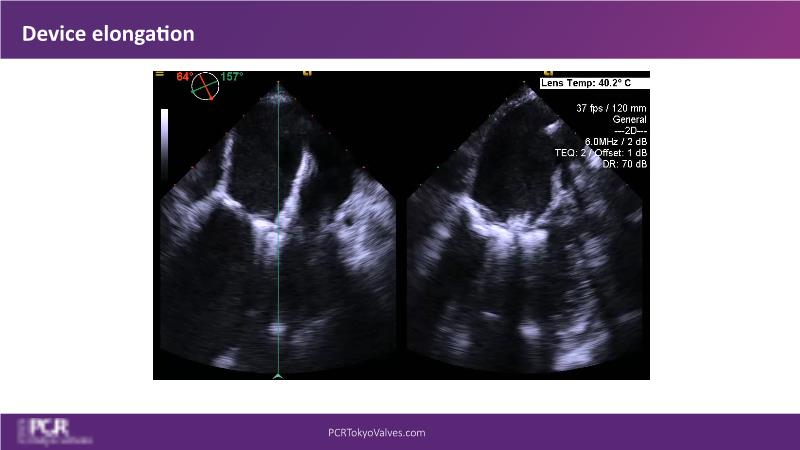

Watch this session to get an overview of a new TEER device, follow the step-by-step procedure related to initial experiences with this device for a Japanese patient with degenerative mitral regurgitation, learn about the latest data from RCT and registries, and follow discussions of challenging TEER cases!

- To learn procedural step-by-step of novel device